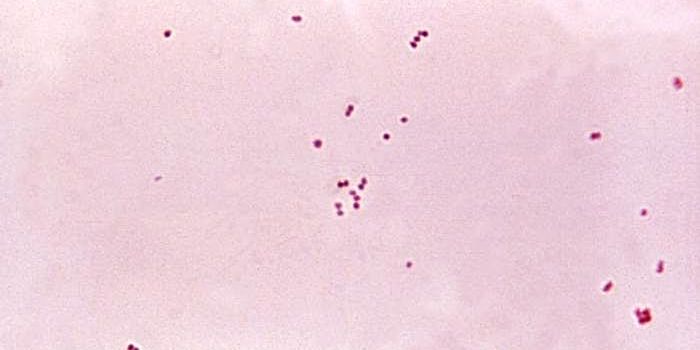

SEP 13, 2015MicrobiologySalmonella enterica are a group of rod shaped bacteria that are most commonly associated with foodborne illness in human ...

JUN 25, 2015Health & MedicineSalmonella enterica is the number one cause of bacterial foodborne illness worldwide. Infections can be transmitted by a ...